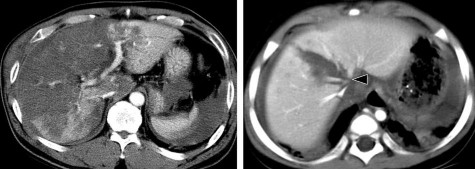

Hình 1.17. CTG độ III. Tụ máu góc dưới thùy gan phải (mũi tên) > 10cm.

Hình 1.18. CTG độ III. Rách nhu mô gan > 3cm thùy gan phải, chảy máu.

Nguồn: Shanmuganathan K, Mirvis SE [21].

Hình 1.19. CTG độ IV. Rách nhu mô

> 50% thùy gan phải.

Hình 1.20. CTG độ IV, rách nhu mô nhiều hạ phân thùy gan T.